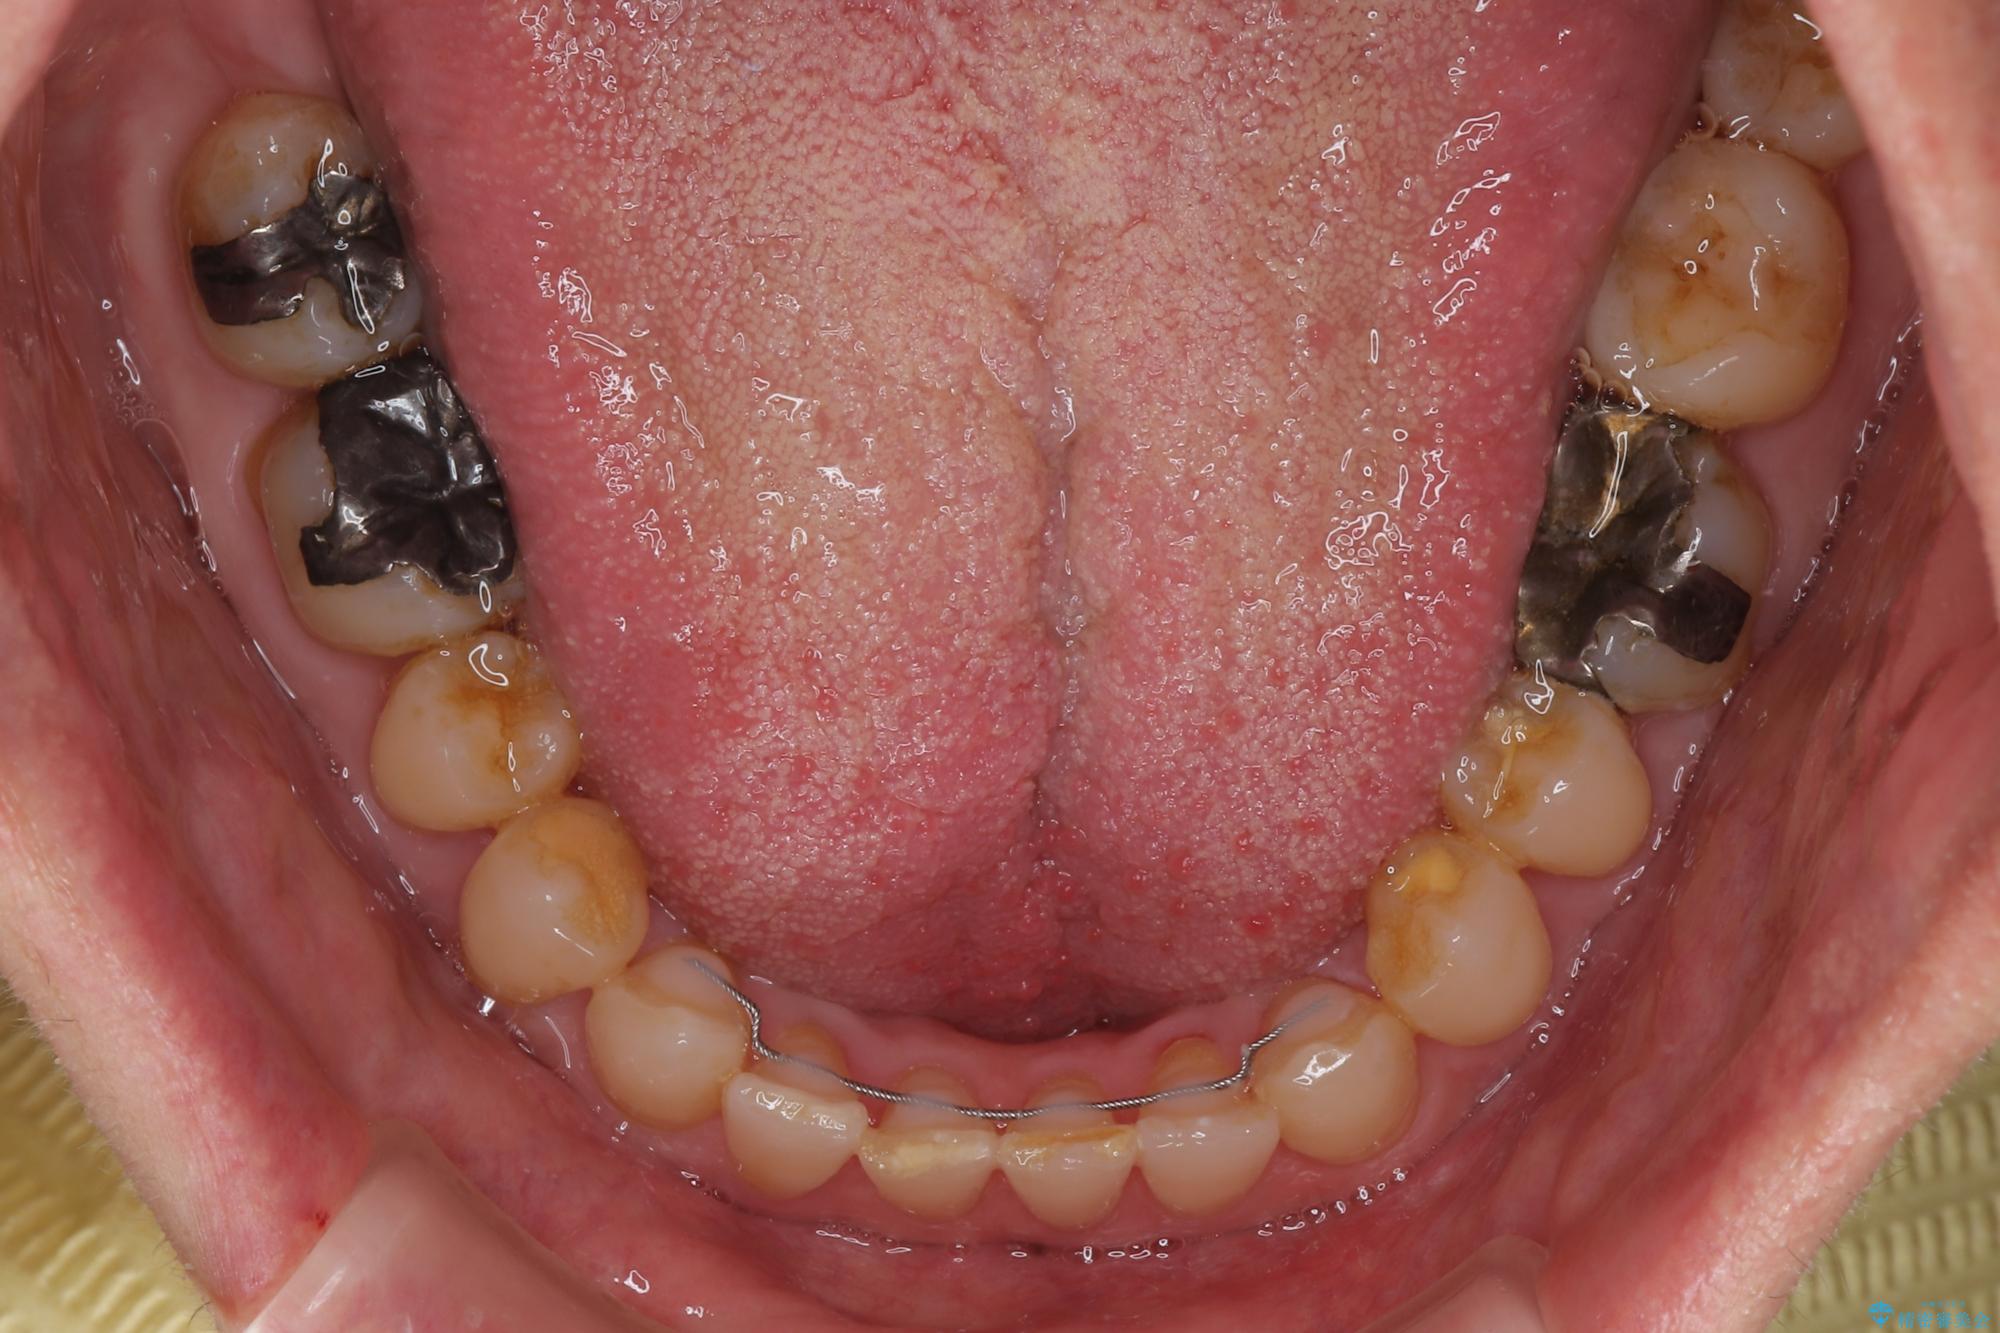

- 前歯のデコボコと隙間の空いた歯列を気にして来院された患者様です。

下顎前歯が隠れるほどのディープバイトにより、強い咬合力と突き上げで上顎歯列に隙間が空いている状態でした。

手前に傾斜している奥歯をワイヤー装置で立ち上がらせ、咬み合わせの高さを挙上することで突き上げを解消し、空隙歯列を改善していくこととしました。